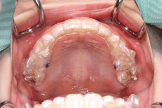

小学生のマウスピース型矯正装置とその他の装置(拡大床)の比較

拡大床の場合

治療のゴールは、顎の大きさを広げるのみです。

• 治療期間は、6~24か月。(※個人差あり)

• 取り外しは、できません。

• 基本的には、2年間同じ装置を使用します。

• 見た目は、針金が少し目立ちます。

• シミュレーションソフトは使用しません。

マウスピース型矯正装置の場合

治療のゴールは、顎の大きさを広げるだけではなく、それと同時に気になっている歯のねじれやガタガタ、隙間などに対しても細かく歯の位置を修正することです。

• 治療期間は、18か月。

• 取り外しができます。食事や歯磨きも普段通りに行えます。矯正装置による虫歯のリスクは固定式の装置に比べ格段に少ないと考えられます。

• 定期的(平均2週間に1度)に新しいマウスピースに交換していくので衛生的です。

• 透明なマウスピースを装着するので、装置をつけていても目立ちません。

• シミュレーションソフトによる治療計画の立案と治療中の経過検証が可能です。